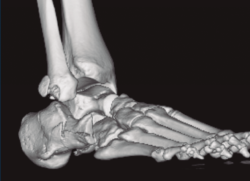

Figura 2. Fractura maléolo peroneo y tibial posterior. Trazo entre fragmento anteromedial y posterolateral.

Figura 3. Desplazamiento entre fragmento anteromedial (sustentaculum tali) y posterolateral (tuberosidad).

Se trata de un varón de 19 años que ingresa en reanimación tras precipitarse desde una altura de aproximadamente 10 metros. El paciente presenta una fractura estallido de L3 con afectación del canal medular junto con una fractura del vértice inferior de L4, así como una fractura luxación de calcáneo, asociada a una fractura del maléolo peroneo y del maléolo tibial posterior (Figuras 1 a 6) diagnosticadas mediante TC total body (por eso no se dispone de radiografías simples al momento del ingreso). Como podemos comprobar, se trata de una fractura de doble trazo de tipo hundimiento/depresión de la carilla articular (Figuras 5 y 6).

Figura 4. Luxación fragmento posterolateral.

Figura 5. Fractura maléolo peroneo, luxación astrágalo, fractura de doble trazo en calcáneo.

Figura 6. Fractura de doble trazo; se evidencia afectación de la articulación calcaneocuboidea.